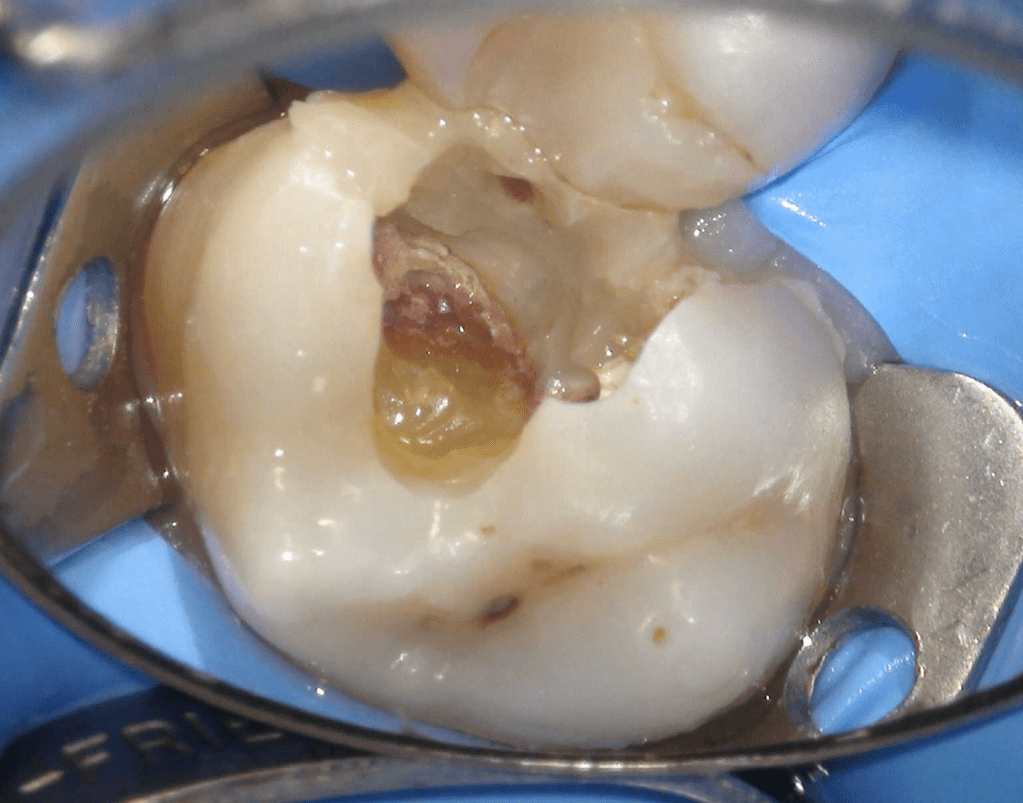

Pulpotomía biodentine + reco preendio